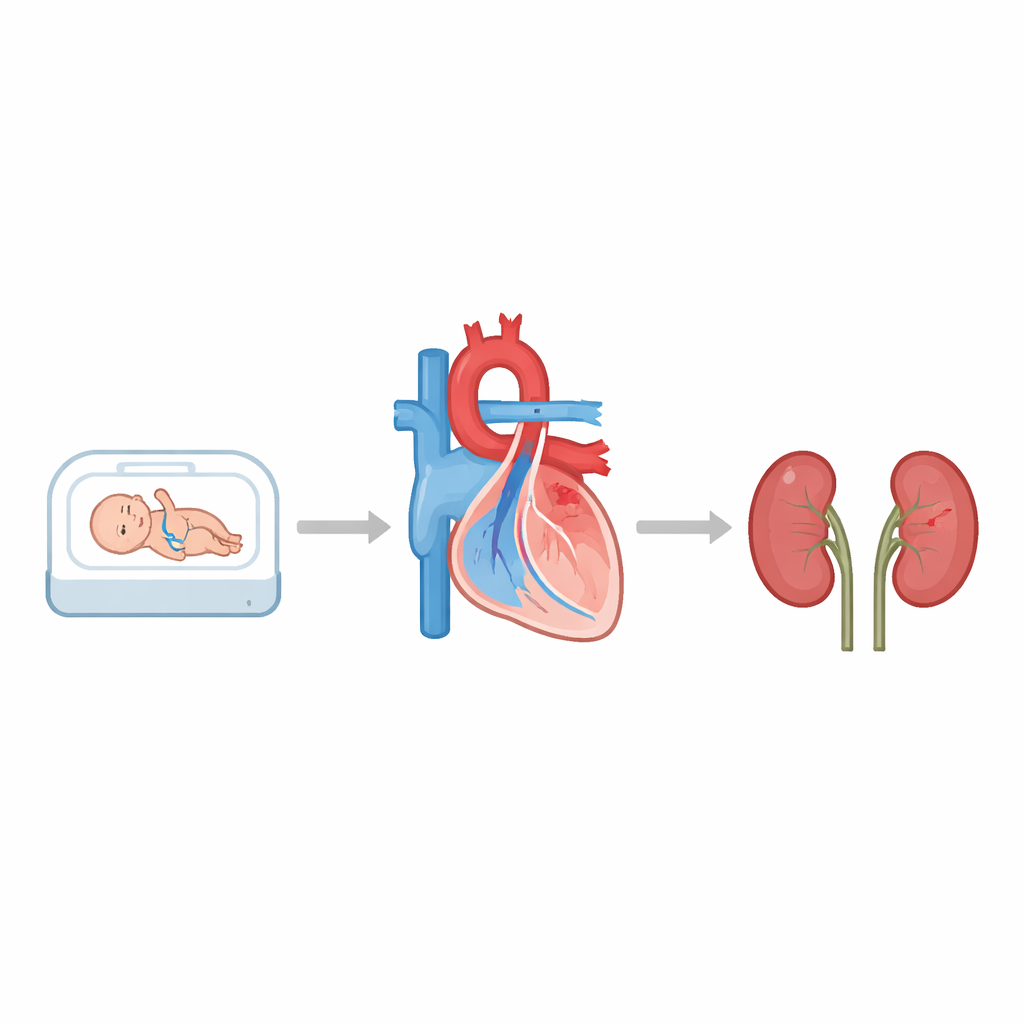

Quando i bambini nascono estremamente precocemente, ogni organo è ancora in fase di sviluppo. I medici si preoccupano molto del cuore e dei polmoni, ma anche i reni—i nostri filtri naturali—sono molto vulnerabili. Questo studio ha posto una domanda mirata: se un grande vaso sanguigno vicino al cuore nei neonati molto prematuri rimane aperto a lungo, quella pressione aggiuntiva sulla circolazione rende più probabile un danno renale grave settimane dopo?

Prima della nascita, i bambini hanno un breve vaso sanguigno chiamato dotto arterioso che aiuta a bypassare i polmoni. Dopo la nascita dovrebbe chiudersi. Nei neonati molto prematuri, tuttavia, spesso rimane aperto; i medici lo chiamano dotto arterioso pervio, o DAP. Quando il DAP è ampio e influisce fortemente sul flusso sanguigno, può sottrarre sangue al corpo e ai reni e convogliare troppo verso i polmoni. Allo stesso tempo, molti ospedali hanno adottato un approccio più conservativo di osservazione anziché chiudere subito i DAP con farmaci. Questo significa che alcuni neonati fragili possono convivere con questo vaso cardiaco aggiuntivo per mesi, sollevando il timore che i loro reni possano subirne le conseguenze nel tempo.